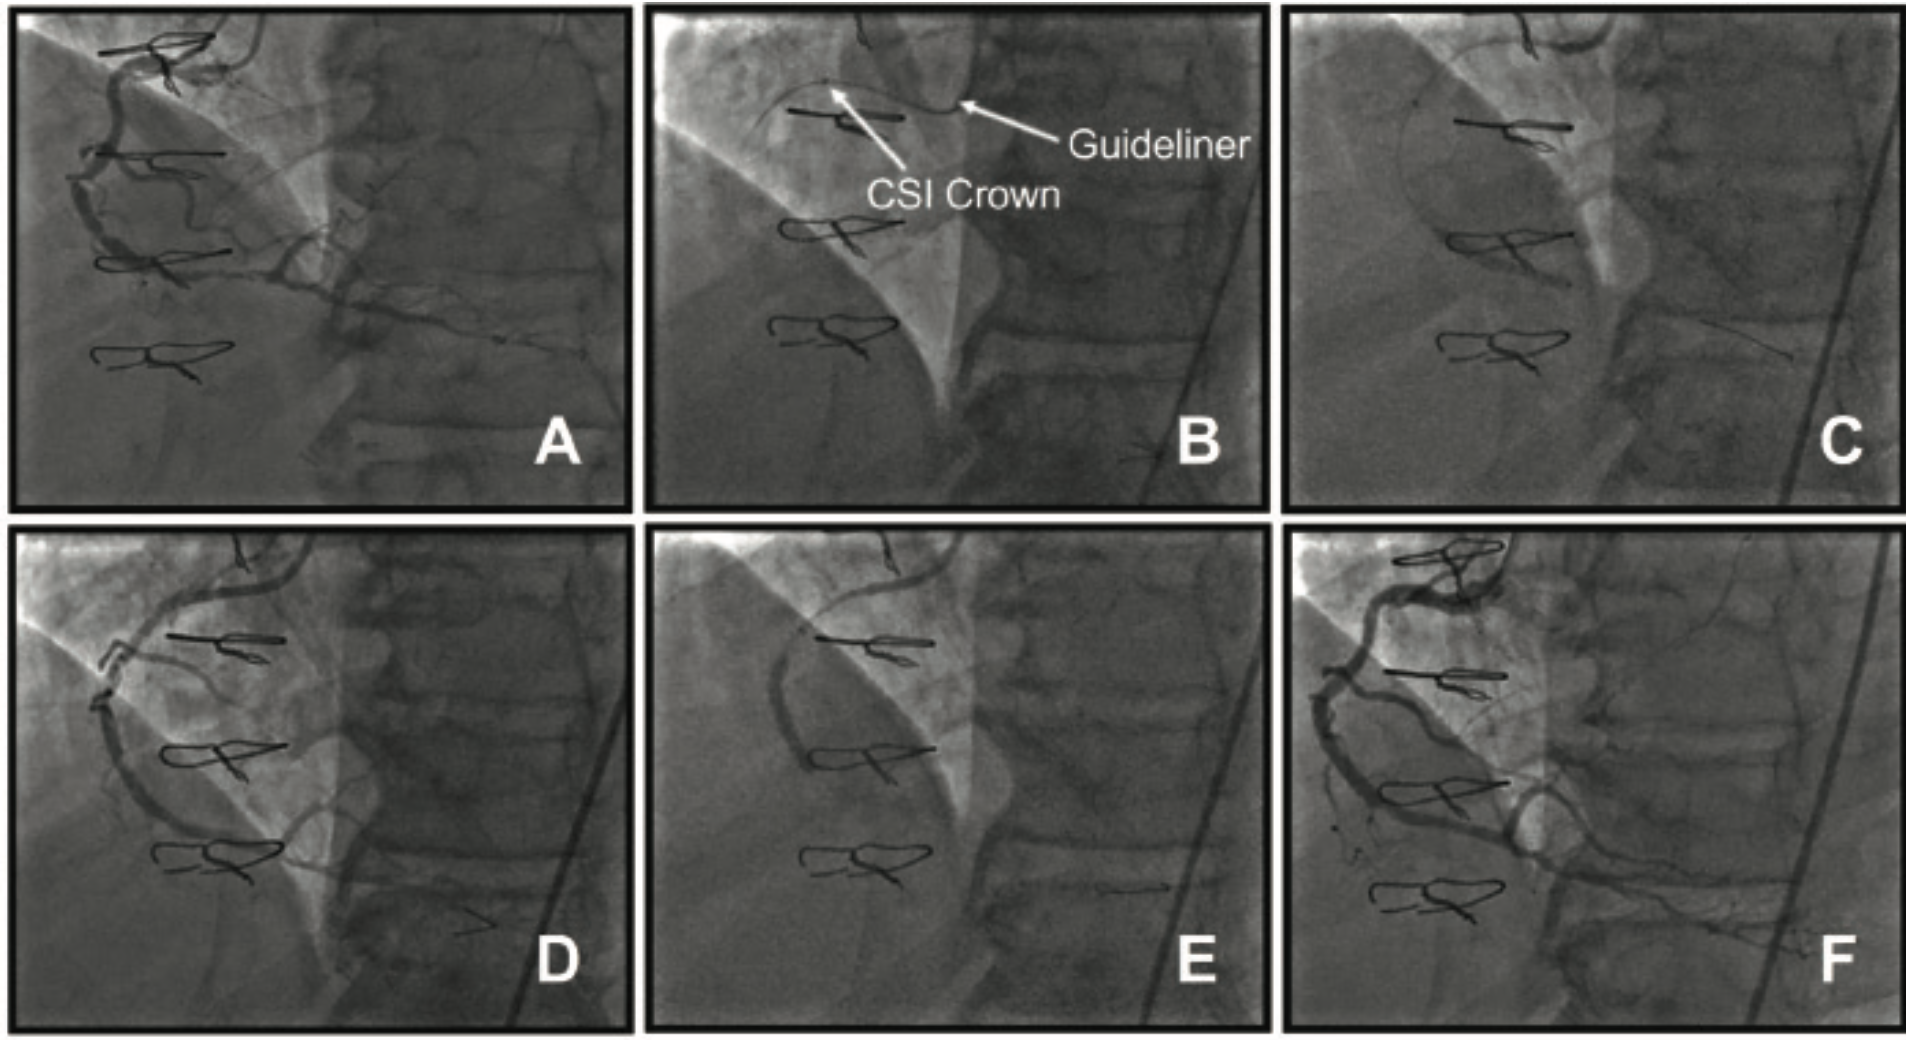

Transfemoral coronary angiography was performed using a 7.0 Fr, 10 cm sheath using the modified Seldinger technique. The RCA was engaged with a JR4 catheter (Figure 2A). A Choice PT wire was advanced to the distal RCA. Using GuideLiner assistance (Figure 2B), an OTW balloon was advanced beyond the mid RCA lesion and into the distal vessel. This was then exchanged for a 300 cm Viper wire. With GuideLiner assistance, the Diamondback OA system with a 1.25 mm crown was placed at the origin of the lesion and orbital atherectomy was performed at 80,000 revolutions per minute (rpm) for multiple runs at less than 30 seconds per run, followed by a 30-second pause. Continuous flush was performed with normal saline with 5 mg of verapamil and 20 cc of ViperSlide lubricant (CSI). The Diamondback system was removed. Optical coherence tomography (OCT) was done to assess length and diameter of stent required. The mid RCA was stented using two overlapping stents (Resolute Integrity DES 2.5 mm x 30 mm distally [Figure 2C] and 3.0 mm x 26 mm proximally [Figures 2D-E]). The entire mid-RCA stented area was post-dilated with the stent balloon. The final view (Figure 2F) demonstrated excellent angiographic results and adequate stent expansion with TIMI-III flow in the RCA. The patient was observed overnight and discharged on 81 mg aspirin and 75 mg clopidogrel.